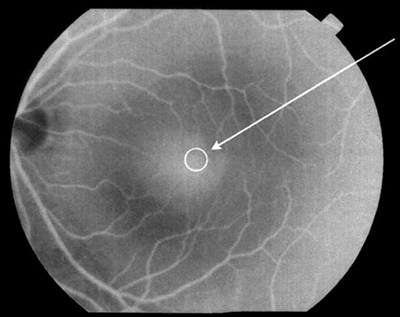

A macular hole is a small, circular gap which opens up at the centre of the retina.